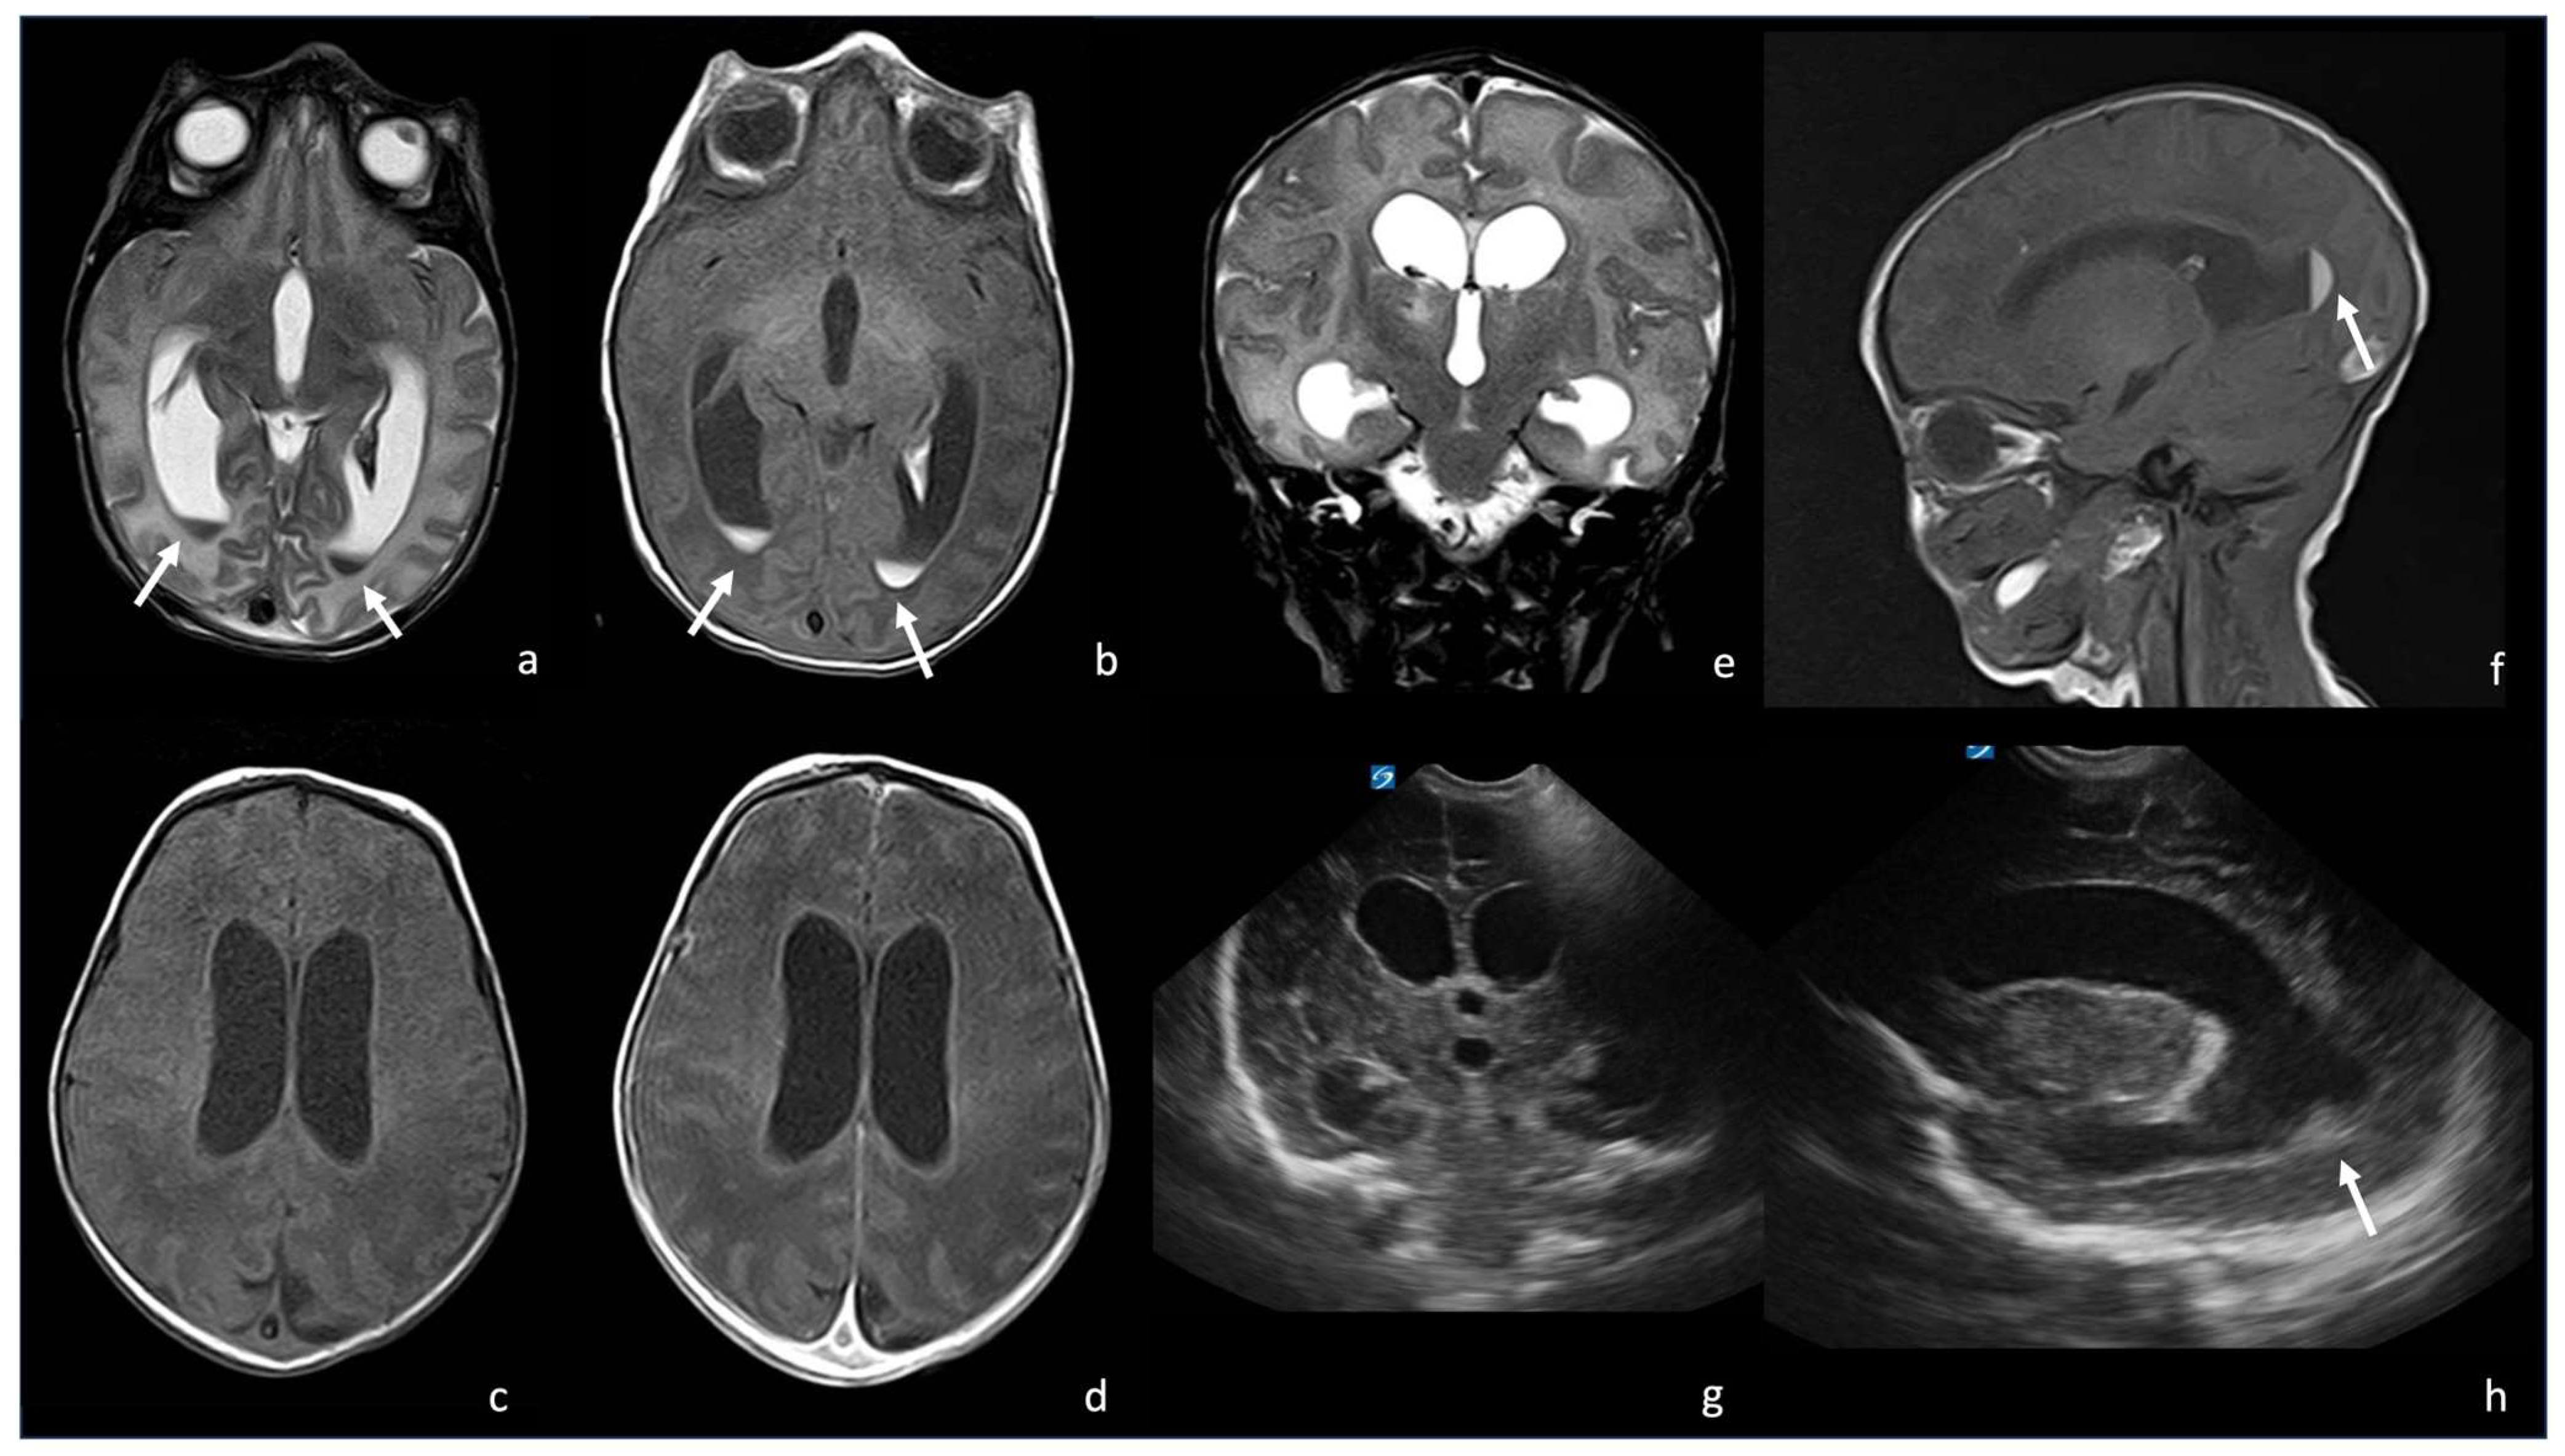

Figure 10.

Three different cases of newborns with brain sequelae caused by Listeria Monocytogenes meningoencephalitis. The first case (a–e) refers to a boy of 9 days of life, who presented with meningoencephalitis characterized by ventriculitis with enlarged ventricles ((a), axial T2WI) with ependymal contrast enhancement (arrow in (b), axial post-contrast T1WI) and an encapsulated abscess in the right white matter (arrow in (c), axial post-contrast T1WI). At the 3-month FU, the brain MRI showed massive cystic encephalomalacia and periventricular cavitations (arrowheads in (d,e), axial T2WI). The second case (f,g) shows the 3-month FU MRI of a girl affected by listeria meningoencephalitis at 6 days of life, evolved in multiple periventricular cysts (arrows in (f), axial and (g), coronal T2WI). The third case (h,i) refers to a boy who presented with Listeria meningoencephalitis at 5 days of life, whose 2-month FU MRI showed encephalomalacia with multiple cysts (arrow in (h), axial and (i), coronal T2WI).